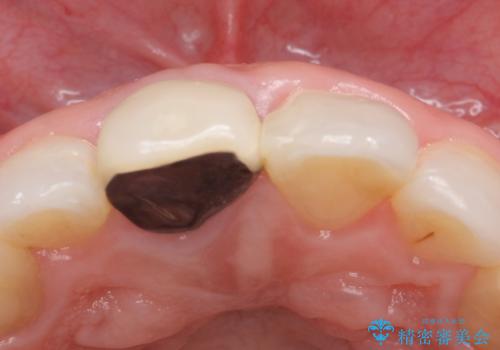

- 右上1の前歯の見た目が気になるので被せ物をやり替えたいといらっしゃった方の症例です。

再根管治療終了後、オールセラミッククラウン(スペシャル)によって隣在歯に合わせた補綴を行いました。